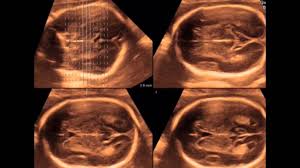

Nub Theory How To Predict Your Baby S Sex At 12 Weeks

Nub Theory How To Predict Your Baby S Sex At 12 Weeks from keyassets-p2.timeincuk.net

This is between 11 weeks and 13 weeks plus six days, to be exact (nice 2008), or when your baby's crown rump length (crl) is between 45mm (1.8in) and 84mm (3.3in). You can discuss whether you want or need a dating scan with your doctor or midwife. Check 'anomaly' translations into tamil. You can also listen to your baby's heartbeat during this scan. A nuchal scan or nuchal translucency ( nt) scan / procedure is a sonographic prenatal screening scan ( ultrasound) to detect chromosomal abnormalities in a fetus, though altered extracellular matrix composition and limited lymphatic drainage can also be detected. A dating scan might be recommended before 12 weeks to confirm your due date if you are unsure of your last menstrual period or your date of conception. The sonographer will measure the baby and use these measurements. The presence of a heart beat.